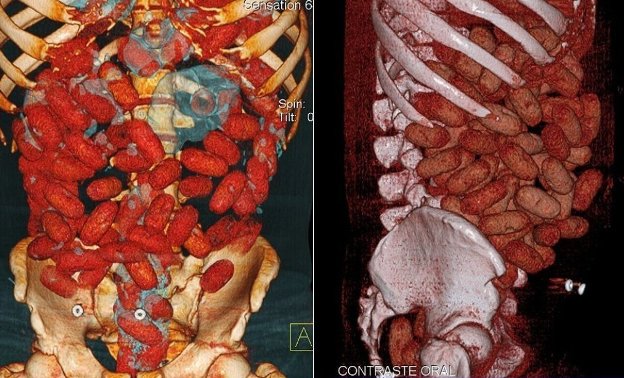

cocaine

CAT SCAN: In this Monday Sept. 12, 2011 image of a CAT scan released by Brazilian Federal Police on Sept. 16, 2011, bags loaded with cocaine are seen inside the body of an unidentified man after he was arrested at the Congonhas airport in Sao Paulo, Brazil on Monday. According to a federal police press release, the man is identified as a young Irish male who tried to board a flight to Brussels after swallowing 72 capsules containing a total of 830 grams.